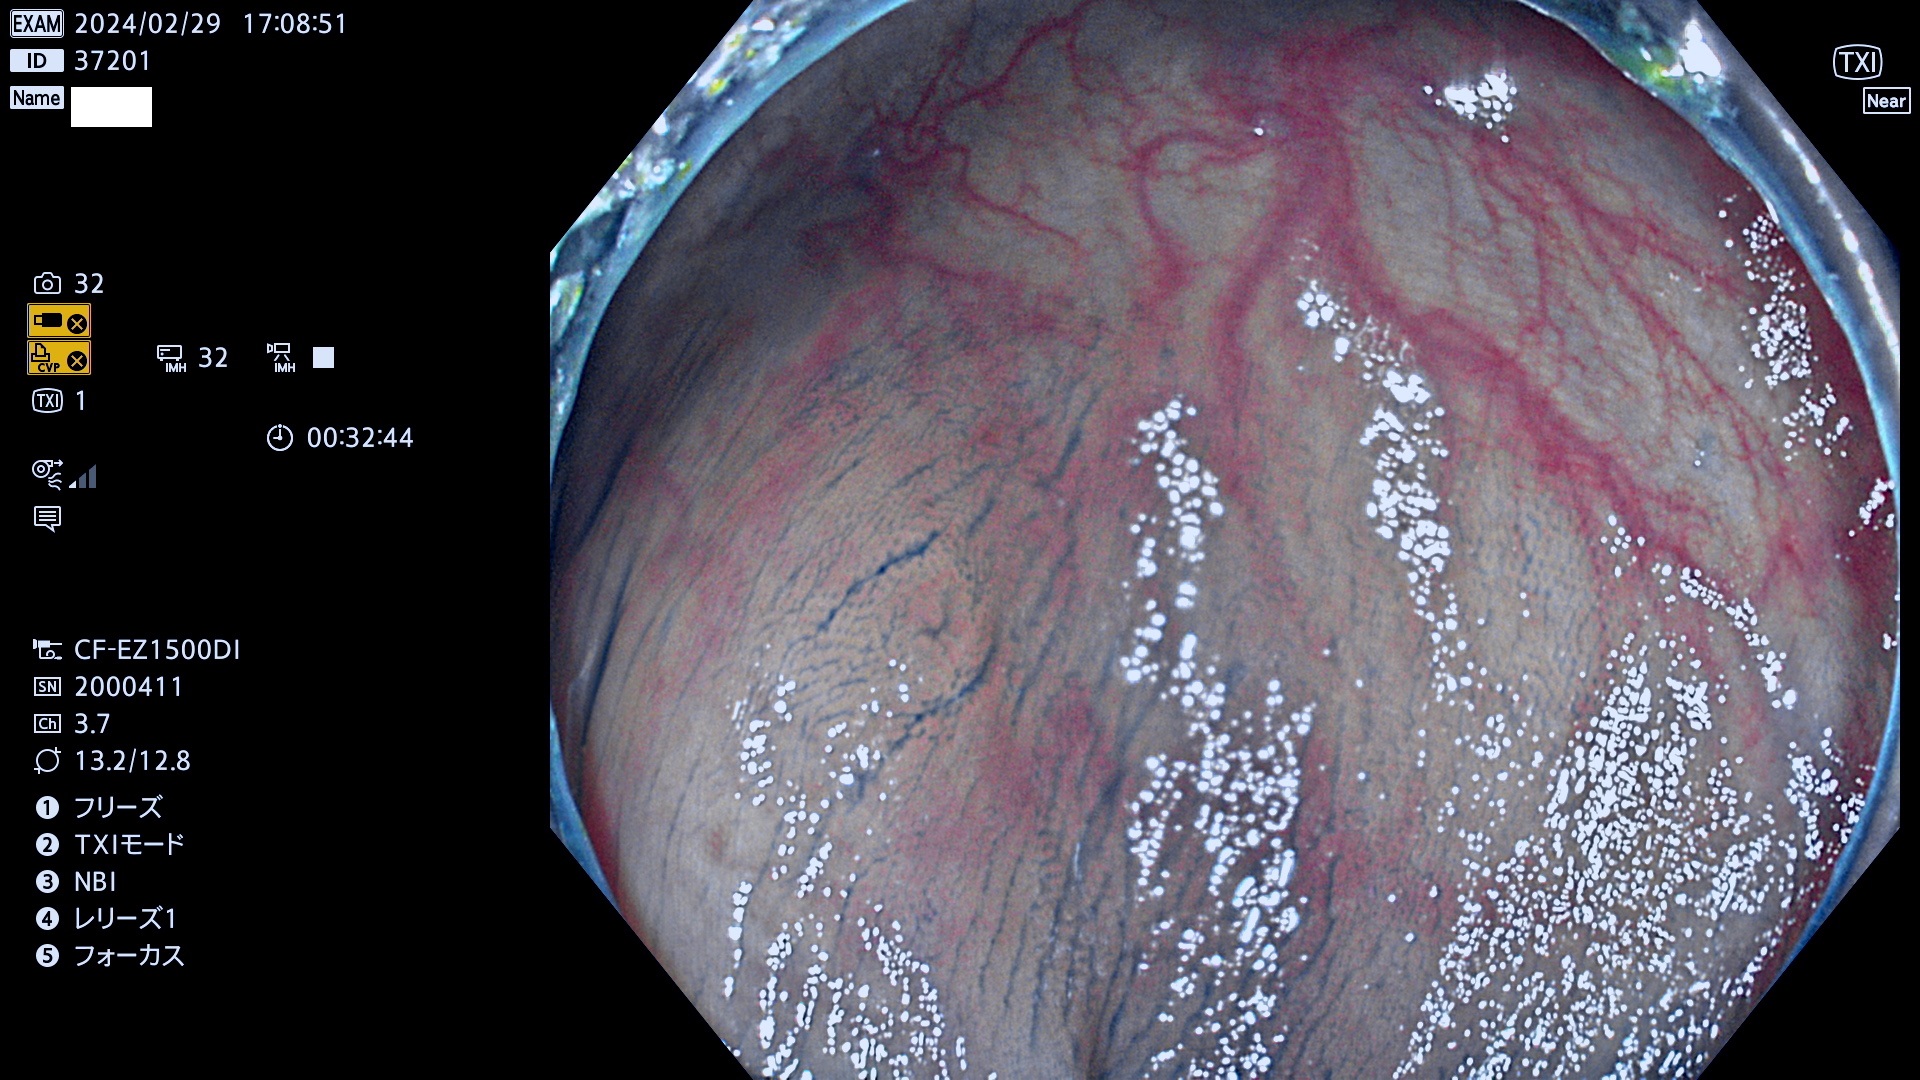

表面型腺腫(Flat Adenoma)の中で、完全に平坦な物をUb、陥凹している物をUcと呼びます。平坦隆起型(Ua)よりも、発見が難しく危険な病変です。

専門的)Uc=De Novo癌? 内視鏡の解像度が低かった時代、このような説もありました。しかし今日の高精度内視鏡では良性の微小なUc型腺腫が日常的に見つかります。私見ですが「Ucこそが多段階発癌(Adenoma-Carcinoma Sequence)のMain Route」と考えます。

毎週の検査(木・金・土・日)に発見されたUb、Uc型・腺腫を、その週の日曜の夜にUPし1週間、提示します。

抽出の対象期間 2024年2月29日(木)〜3月4(日)の5日間(50件の検査)4件 (4/50=8%)